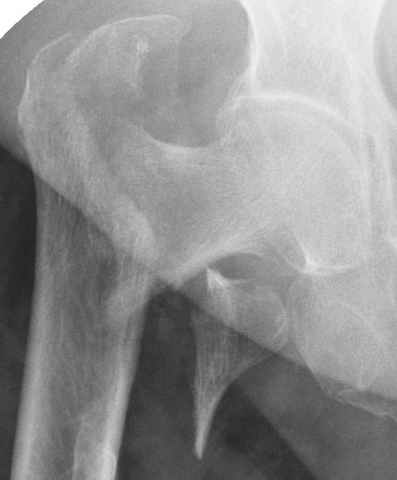

Уважаемые коллеги.Ко мне обратился мой коллега, весьма опытный травматолог, владеющий практически всеми видами остеосинтеза, с просьбой собрать мнения по поводу нескольких клинических случаев - два перелома бедра и перелом плеча.Если можно, подтвердите свое мнение иллюстрациями аналогичных ситуаций, либо ссылками - для клинического разбора. Бедро 1:Женщина 1929 г.р. Травма в результате падения 14.09.04г.Диагноз Закрытый оскольчатый чрезвертельный перелом правой бедренной кости со смещением отломков.Сопутствующие заболевания: ИБС, стенокардия напряжения, постинфарктный кардиосклероз (ИМ в 1992 году); гипертоническая болезнь 2 ст.; ожирение 3. Дополнительные данные - сохранная старушка.Спасибо.С уважением Александр Артемьев

Типичный остеопорозный вертельный перелом , не стабильный, 4-х фрагментный, базоцервикальный. Лечение оперативное не позднее 48 часов после перелома, чем раньше тем лучше, если общее состояние позволяет.